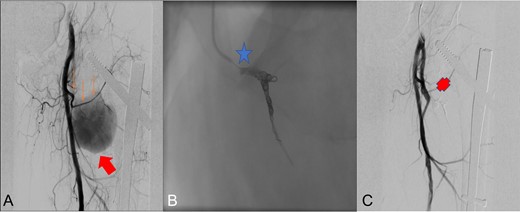

Radioescopic images sequence of the interventional procedure of embolization by retrograde right femoral puncture. A: Lateral femoral circumflex artery (thin arrows) branch of the deep femoral artery, pseudoanerysm (wide arrow). B: Embolization using two Axium 3D distal coils (star). C: Final result with embolized lateral circumflex artery (Cross).